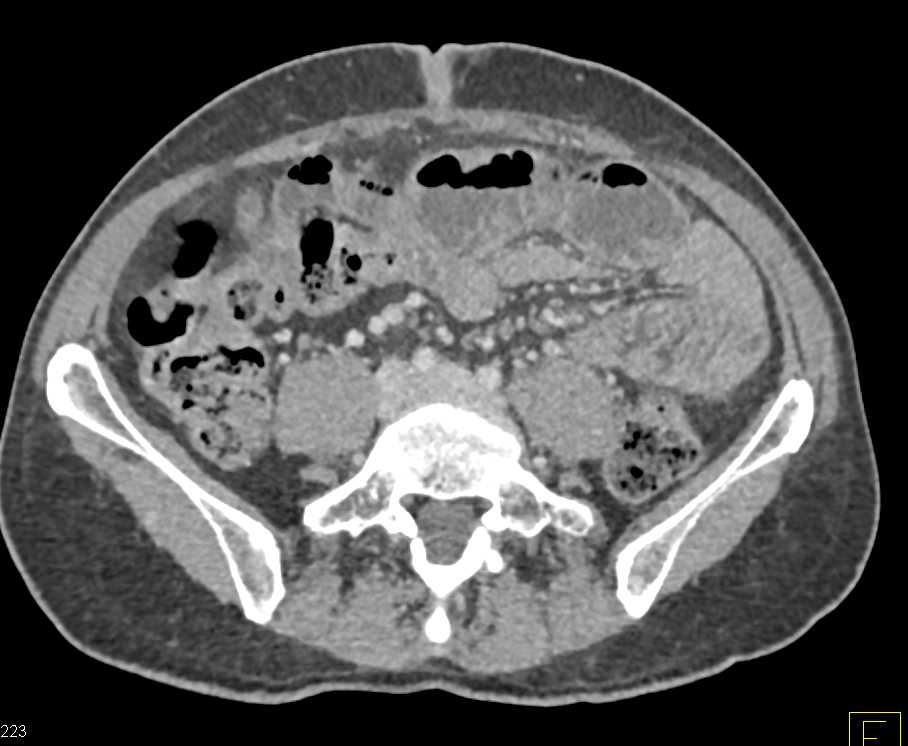

Vasculitis with Superior Mesenteric Artery (SMA) Involvement and Branches